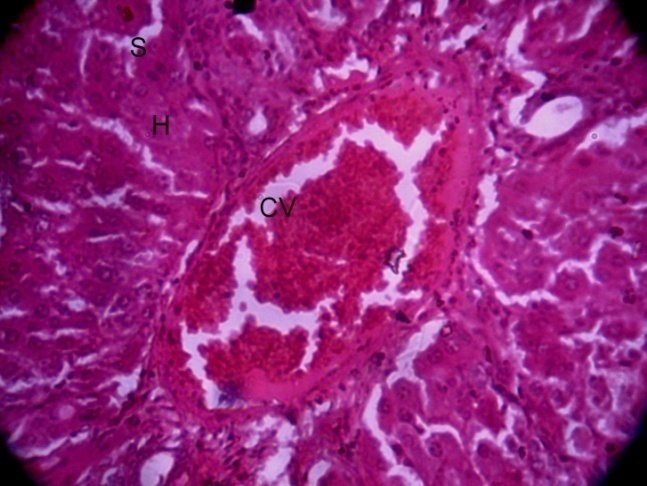

Histopathological examination

The present study is also done to study histopathological alterations in the rat liver, whose autopsy was done after the treatment of 7, 14, and 21 d. Fig. 1 shows a normal histoarchitecture of the liver with a clear CV, H, and S. Fig. 2 shows the structure of the liver after 7 d of treatment with the standard drug (Silymarin). The present study is also done to study histopathological alterations in the rat liver, whose autopsy was done after the treatment of 7, 14, and 21 d. Fig. 1 shows a normal histoarchitecture of the liver with a clear CV, H, and S. Fig. 2 shows the structure of the liver after 7 d of treatment with the standard drug (Silymarin). The CV is filled with RBC and damaged cells, and a fatty layer surrounds the CV, but the fat layer is thinner than that of rats treated with other formulations (fig. 3). With the treatment of Formulation-II, more damage was seen than with Formulation-I and the standard drug. CV is filled, and a thick fatty layer is present around CV. Hseem to be damaged, and S seem to be dilated due to hepatocellular damage (fig. 4). Whereas rats were treated with Formulation-III, hepatocellular damage was clearly seen. CV filled with damaged blood cells and surrounded by thick fatty layer inflammation in H was also clearly visible here; due to which S are compressed (fig. 5). In the experimental group, H seem to be more damaged than in other groups, where some air filled space was also observed due to hepatocellular damage. A fatty layer surrounds the CV, and vast damage was also noticed (fig. 6).

Fig. 2: After 7 d of treatment with the standard drug, showing damaged hepatic cells with blood-filled CV (H and E stain 100X).

Fig. 2: Standard |

After 14 d

In normal control, there was no evidence of any kind of hepatocellular damage presented during the histological examination (fig. 7). With the treatment of the standard drug, there was a slight recoupment as compared to 07 d. The CV seems to be clearer after 7 d of examination, and the fatty layer seems to be thinner as well (fig. 8). In the rats treated with formulation-I, a clear difference was seen after 7 and 14 d of examination. H cells seem to be repaired, and CV shows a clear lumen (fig. 9). Formulation-II recoupment seems to require more than a 7 d histological examination. But, hepatocellular damage was present. CV seems to be filled with fluid. A thick cellular layer surrounds the CV (fig. 10). Formulation-III treatment for 14 d showed less recoupment than other formulations (I and II) and the standard drug. CV is filled with damaged cells and surrounded by a thick layer (fig. 11). In the experimental group, there is no evidence of self-recoupment presented here without any treatment. Much more hepatocellular damage was seen as compared to other groups (fig. 12).

Fig. 8: After 14 d of treatment with the standard drug, there is a slight recoupment with a thinner fatty layer around CV and less fluid in CV (H and E stain 100X).

Fig. 8: Standard |